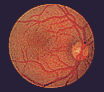

Augenhintergrund Die am häufigsten verwendete Untersuchungsmethode des Augenarztes ist die Augenspiegelung. Mit Hilfe des Augenspiegels, des Ophthalmoskops, kann der Arzt den Augenhintergrund im hinteren Bereich des Auges des Patienten beleuchten. So ist eine genaue Untersuchung der Netzhaut und der Gefäße möglich. Der Punkt des schärfsten Sehens (Fovea centralis) und der Eintritt des Sehnervs werden sichtbar. Die nebenstehende Abbildung zeigt einen normalen Augenhintergrund.